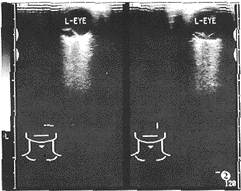

1.原发性部分性视网膜脱离:①玻璃体内出现异常带状高回声,后端连于视乳头,前端 粘附于锯齿缘(图1)。②横向扫查时带状高回声隆起呈弯曲的波浪状或弧形隆起,纵向扫 查时病理带状高回声与眼球壁平行,各径线隆起程度一致(图2)。③转动眼球时,玻璃体 内可见带状高回声轻度震颤或飘浮隆起不一致。④脱离的视网膜带状高回声后面为经裂洞进 入的视网膜下液,前面为玻璃体液。

图2 部分性视网膜脱离,横向扫查带状高回声呈弯曲的波浪状或弧形隆起,纵向扫查带状高回声与眼球壁平行,各径线隆起程度一致